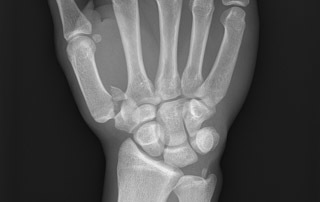

Initial investigation for a suspected scaphoid fracture?

Scaphoid series of X-rays (4 views)

What are the 4 scaphoid X-ray views?